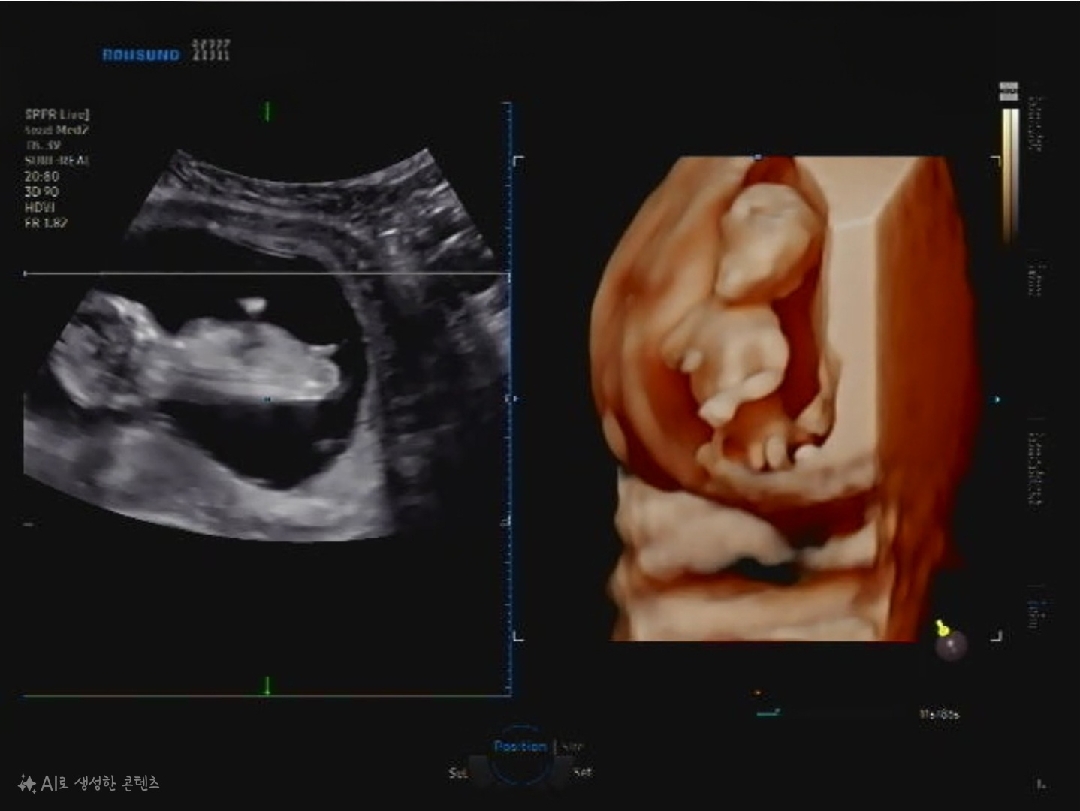

12주4일차 사진이에요ㅎㅎ

빌리는 아들인거같다는데 여러분들 생각은 어떠신가요?!! 아들이든 딸이든 상관없지만 너무 궁금하네요😆😆